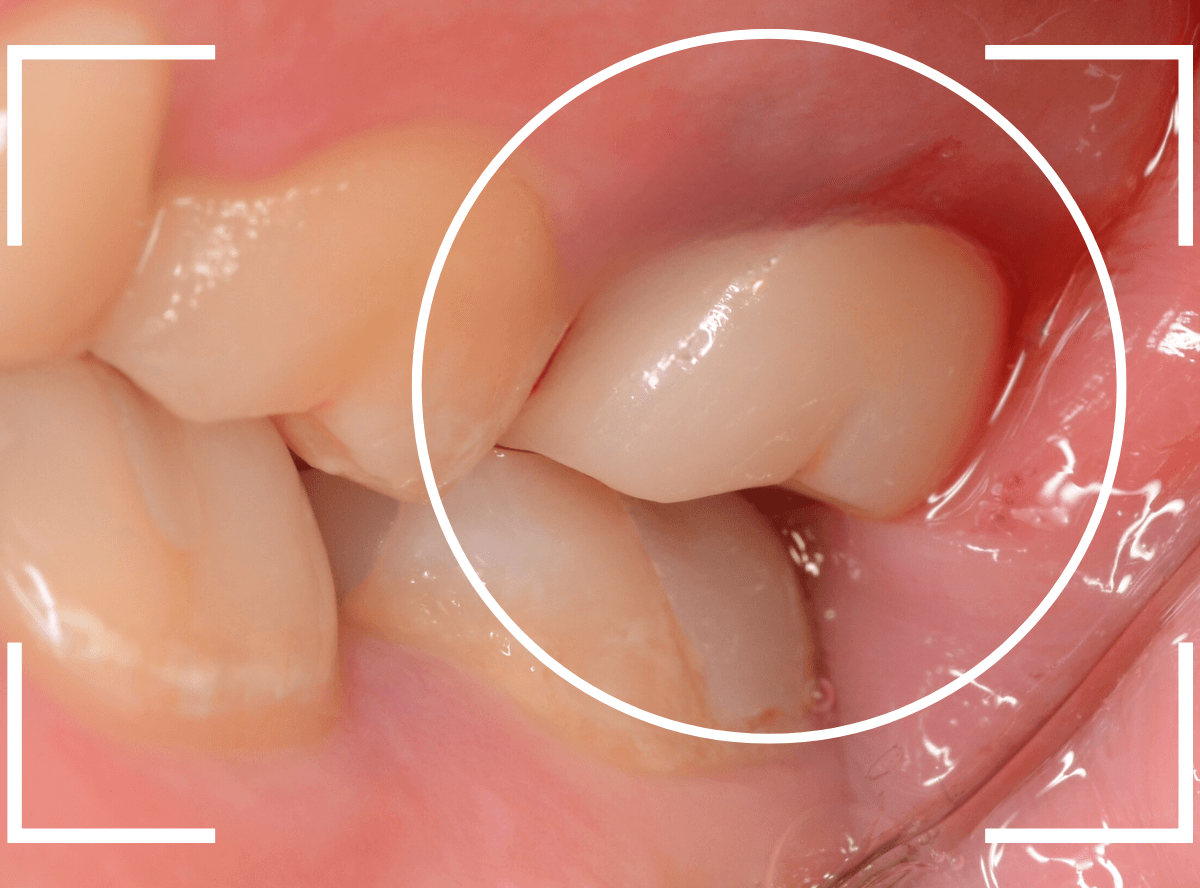

歯の神経の治療後、土台まで作って長期間放置してしまった方です。

このような方は多く見受けられます。

ご本人には「痛くもないし、少し咬みづらい」くらいの感覚かもしれませんが、この状態で放置すると、歯はない方に動く習性がありますので、咬み合わせる反対の歯がずれてきてしまい、さし歯を作る際の支障になってしまいます。

この方も、反対の歯が大分ずれてきてしまいましたので、歯を大きく削る必要があり、調整に苦労しました。